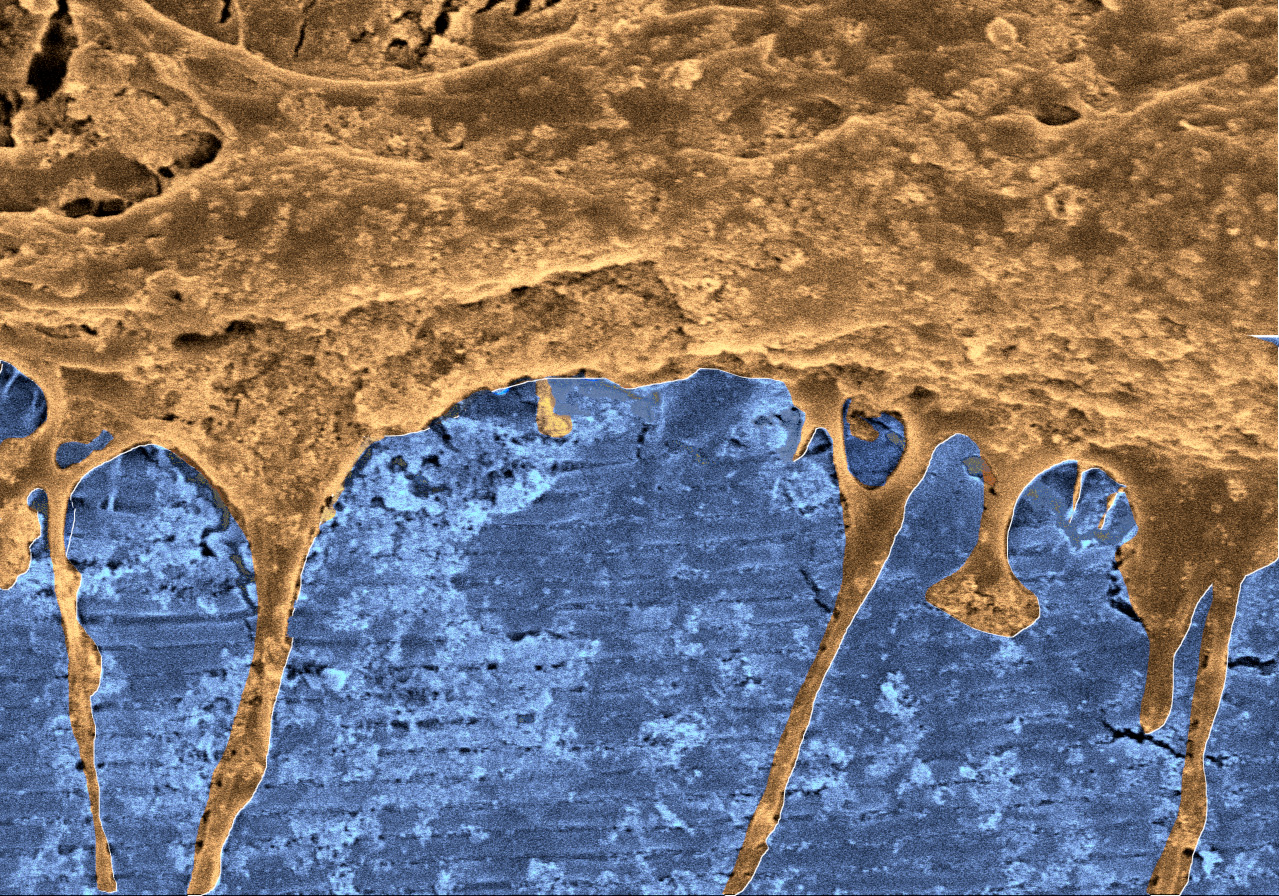

Scanning electron microscopy photograph showing, firstly, the nanostructured scaffolding (blue), which has been pseudo-coloured and in which it is possible to see the horizontal nanostructures (as if it were a shutter), and secondly, at the top, the neural stem cells (flesh-coloured) that are aligned in the same direction as the nanostructures (UPV/EHU). -

Thanks to collaboration between the UPV/EHU’s Department of Cell Biology and Histology and the Science and Engineering of Polymeric Biomaterials-ZIBIO Group (BERC POLYMAT), a significant advance in cell therapy has been achieved: "We have constructed bioresorbable elastomeric matrices or scaffolds that combine an ordered nanostructured topography (by way of grooves)together with surface functionalisation with graphene derivatives," explained Dr Aitor Larrañaga, an expert in the design and characterisation of nanomaterials. These scaffolds have enabled "neural stem cells to attach to each other without the need for any other adhesive coating on their surface. Neural stem cells are able to differentiate themselves on the nanostructured scaffolds in vitro, which promotes their aligned migration in cell clusters by following the nanostructured grooves", added Dr José Ramón Pineda, an expert in the field of stem cells.